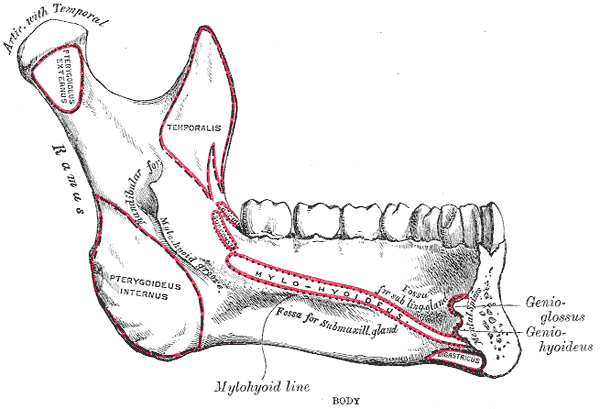

Mandible

- Symphysis & Parasymphysis Body Ramus

- Lingula (小舌)

- Mental spine (頦棘)

- Sublingual g. Mylohyoid line Submandibular g.

- Oblique line

國考毒瘤

肌肉接點